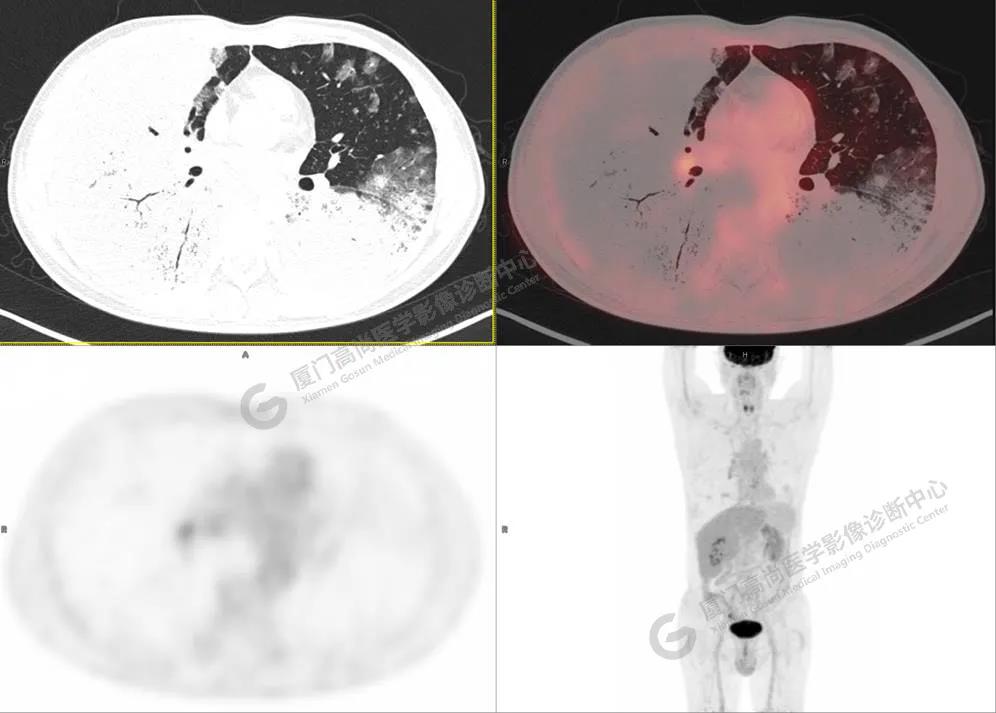

圖4

PET/CT所見:雙肺大片實(shí)變影及磨玻璃影,部分呈地圖樣改變,累及右肺尖,部分放射性攝取輕微增高,SUVmax 1.77,其內(nèi)見多發(fā)支氣管充氣征象。

影像診斷: 雙肺大片實(shí)變影及磨玻璃影,大部分代謝不高,局部代謝輕微增高,考慮肺泡蛋白沉積癥,建議病理學(xué)檢查或肺泡灌洗物檢查。

影像學(xué)表現(xiàn):HRCT上雙肺斑片影,以肺門為中心呈蝶翼狀對稱分布;病變可隨機(jī)分布在中央?yún)^(qū)、周圍區(qū)或全肺葉,病灶與正常分組織分界清楚,呈典型“地圖樣”改變;有支氣管充氣征,但表現(xiàn)為充氣支氣管細(xì)小且數(shù)量及分布稀少;“碎石路”征由彌漫性磨玻璃影及內(nèi)部網(wǎng)格樣小葉間隔增厚組成(鋪路石樣表現(xiàn))。無空洞、蜂窩狀改變、淋巴結(jié)腫大、胸腔積液及明顯實(shí)變等。肺內(nèi)病灶累及范圍、磨玻璃密度高低與PAP患者的病情嚴(yán)重程度相關(guān),嚴(yán)重者病灶累及全肺,同時出現(xiàn)肺內(nèi)大片實(shí)變,并見充氣支氣管征象。PAP影像學(xué)表現(xiàn)程度與臨床癥狀、體征嚴(yán)重程度不成比例,表現(xiàn)為影像改變重,臨床癥狀輕。